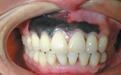

很多人都会关注牙齿,虽然只是关注有没有变黄。但实际上,说出来你可能不信,我们的牙龈,是会得癌的,而且有很明显的特征:牙龈上长有黑斑,也许就是黑色素瘤。和51养生网小编去看看。

牙龈上的黑斑不会痛,也不会痒,导致很多人都以为它是牙龈炎而忽略掉。到后面才发现,这种并不是牙龈炎,而且随着时间,嘴角会流血不止,黑斑块也会慢慢扩散,这个时候,已经晚了,有很大可能是恶性黑色素瘤。

目前,据已知的医学统计显示,黑色素瘤的主要征兆是黑痣、黑色斑块、如果在有这两个的前提下,再出现出血,瘙痒,压痛,面积扩大,硬度增加,溃疡等情况,要警惕癌变了。

癌变的时候,黑色素瘤会在皮肤下面形成肿块,然后就向四面八方扩散,并出现星状的黑斑或小结节。同时,该区域的淋巴结肿大,病情一旦发展至晚期,常见的会转移到肺、肝、骨骼、脑等地方。